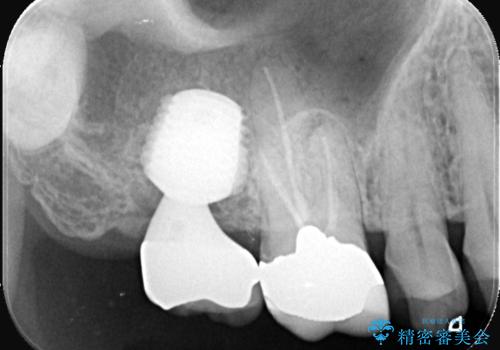

- 治療計画

- 右上7番に瘻孔を認め、根管治療を実施しましたが、瘻孔が再発し治癒が得られなかったため、抜歯のうえインプラントによる補綴治療を行いました。

抜歯と歯根嚢胞の除去を行った後、インプラントで治療しました。治療後は「自分の歯のように咬める」と大変ご満足いただけました。